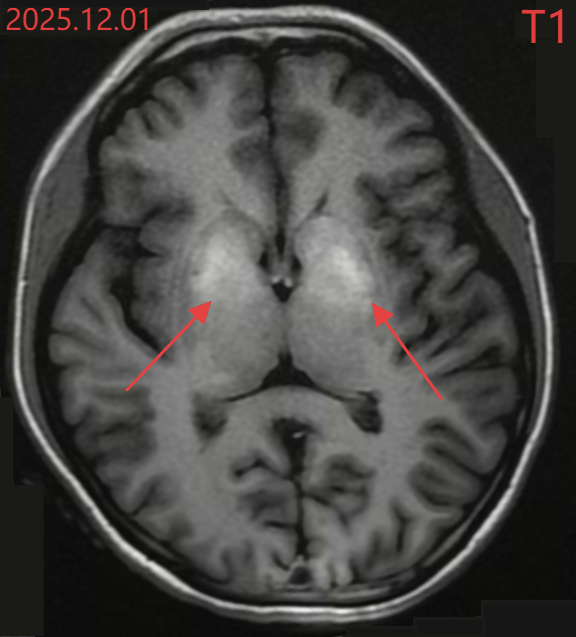

Kết quả chụp cộng hưởng từ sọ não của Tiểu Văn

Các xét nghiệm chuyên sâu sau đó còn đáng lo ngại hơn. Chỉ số HbA1c (đường huyết trung bình trong 2–3 tháng) của Tiểu Văn đạt 17,7%, trong khi mức bình thường cần dưới 6,5%. Điều này cho thấy tình trạng tăng đường huyết đã tồn tại kéo dài trong thời gian dài mà không được phát hiện. Chụp cộng hưởng từ (MRI) não cho thấy vùng hạch nền, khu vực nằm sâu trong não, chịu trách nhiệm điều phối vận động, đã xuất hiện tín hiệu bất thường. Các bác sĩ ví đây như “vết bỏng” của não do đường huyết cao kéo dài gây ra.

Dựa trên lâm sàng và hình ảnh học, bác sĩ chẩn đoán Tiểu Văn mắc bệnh lý vân não do đái tháo đường (DS) . Đây là một biến chứng hiếm gặp của bệnh đái tháo đường, thường gặp ở người lớn tuổi có kiểm soát đường huyết kém trong thời gian dài. Việc bệnh xuất hiện ở một cô gái 20 tuổi, chưa từng được chẩn đoán đái tháo đường trước đó, được xem là trường hợp rất hiếm.